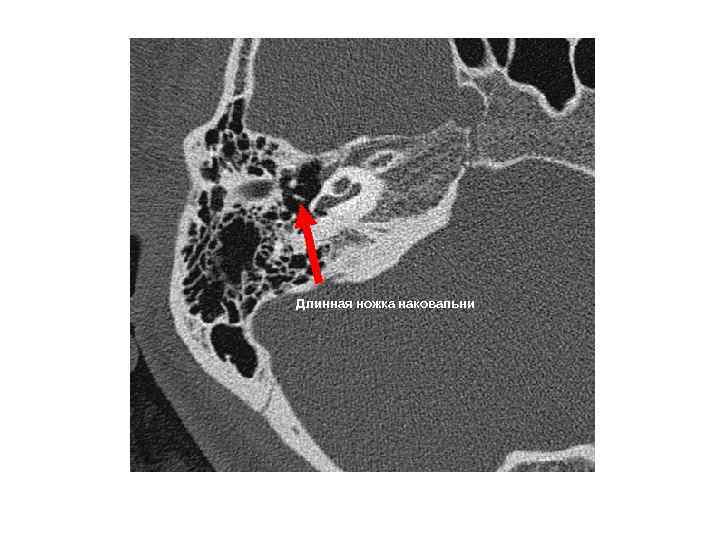

Длинная ножка наковальни Длинная ножка наковальни